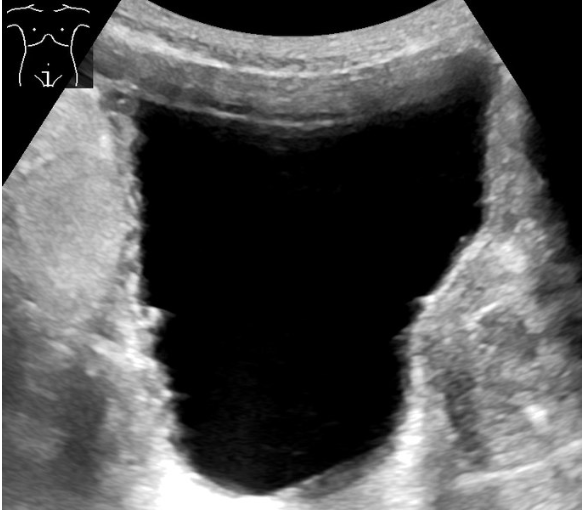

- Other imaging: AXR with IV urogram (most stones not radiolucent and high radiation exposure) or US to assess for hydronephrosis